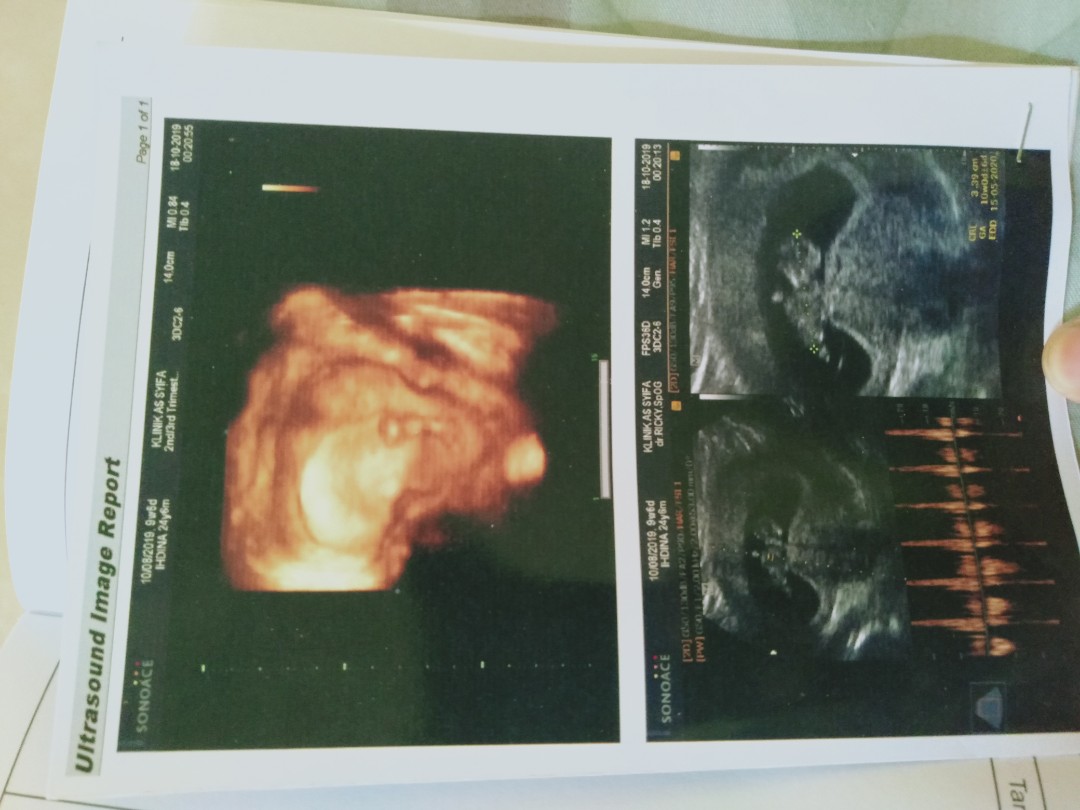

USG

Bund saya mau curhat , Kemaren saya Usg tpi cma keliahatan kantung rahim nya doang , janin nya gk kelihatan , saya sampai bengong dokter bilang begitu , ko bisa janin nya gk keliatan ? perkiraan bidan usia kandungan saya sdh 11 minggu tpi kemaren kta dokter kemaren baru 8 minggu bun, pertanyaan saya bunda Apakah Normal usia kandungan 8 minggu di USG blm keliatan janin nya ? tolong kasih pemasukan bunda saya sampai kepikiran trs dan takut jga ? trimakasih bnyak sebelum nya .